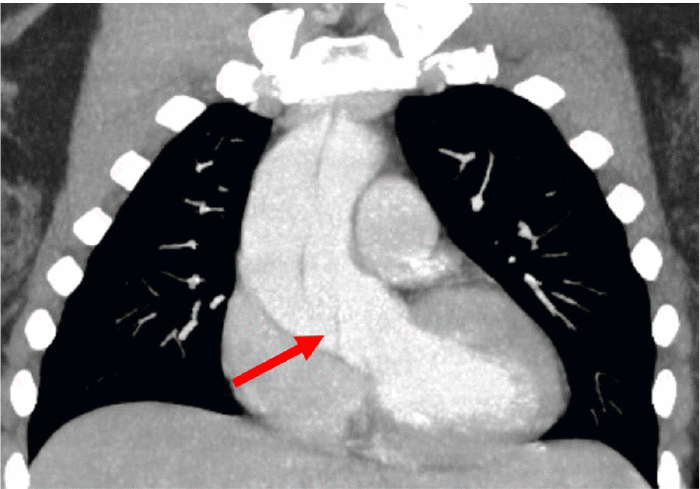

Our patient is a 42-year-old female at 34 weeks gestation with a history of hypertension presented with chest pain radiating to her back. Computed tomographic angiography revealed a Stanford Type A aortic dissection originating near the sinotubular junction and extending distally into the aortic arch and descending aorta (Figure 1).

Figure 1. CT Angiogram. Published with Permission

Stanford Type A aortic dissection originating at the sinotubular junction and extending distally through the aortic arch and into the descending aorta